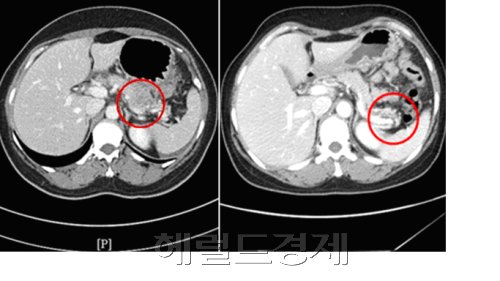

면역유탑 토토사이트법은 각종 TV방송을 통해 소개돼 눈길을 끌기도 했으며, 지난 2009년 8월~11월 사이 면역유탑 토토사이트를 받은 전이암 환자 1년 생존율을 분석한 결과, 유탑 토토사이트 횟수가 늘어날수록 생존율 또한 높아지는 것으로 나타났다고 김 원장은 밝혔다. 지난해 8월 췌장암 진단을 받은 N씨(46)는 임파와 복강 내 전이가 심각해 수술이 불가능한 상황에서 면역유탑 토토사이트를 시작했다. 유탑 토토사이트 기간동안 항암유탑 토토사이트를 병행하며 면역약침유탑 토토사이트 및 온열유탑 토토사이트 등 면역유탑 토토사이트를 받은 결과 췌장 원발 부위 및 임파, 복강 전이 부분의 종양크기가 줄어 들었으며 면역유탑 토토사이트 후 암표지자 수치도 CA125 199.4에서 CA125 27.4로 감소됐다.

<CA125 199.4(사진의 좌)와 CA125 27.4우(사진의 우)>